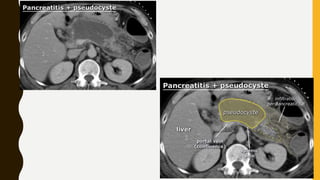

CT IN PANCREATITIS

• When diagnosis is straight forward clinically there may be no need

for imaging. CT may be used to confirm the diagnosis, to assess the

severity of process and look for complication.

• In mild acute pancreatitis, CT may be normal, may show enlarged

edematous gland.

• More sever attack may show peripancreatic fluid collection,

vascular complication such as pseudo-aneurysm and necrosis of

gland itself or surrounding fat.

• Necrosis typically develop after 48-72 hours after the onset of

symptoms and manifest on CT as lack of enhancement of the area.